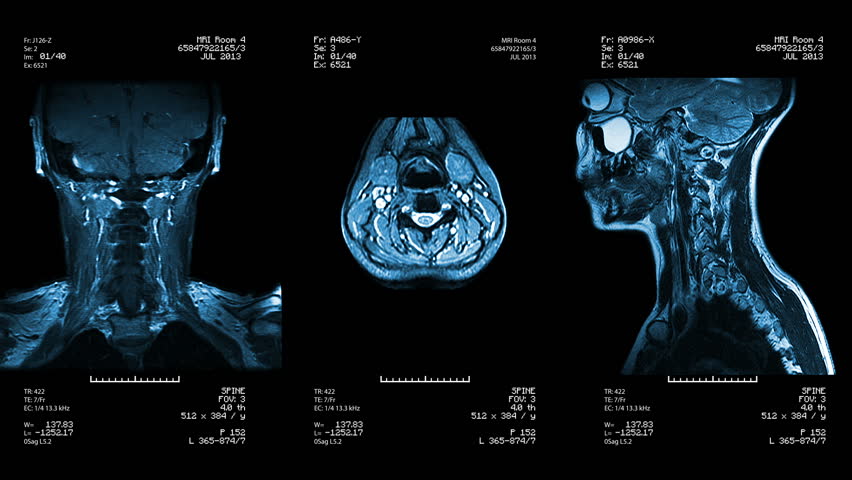

2.CT scan & MRI details.